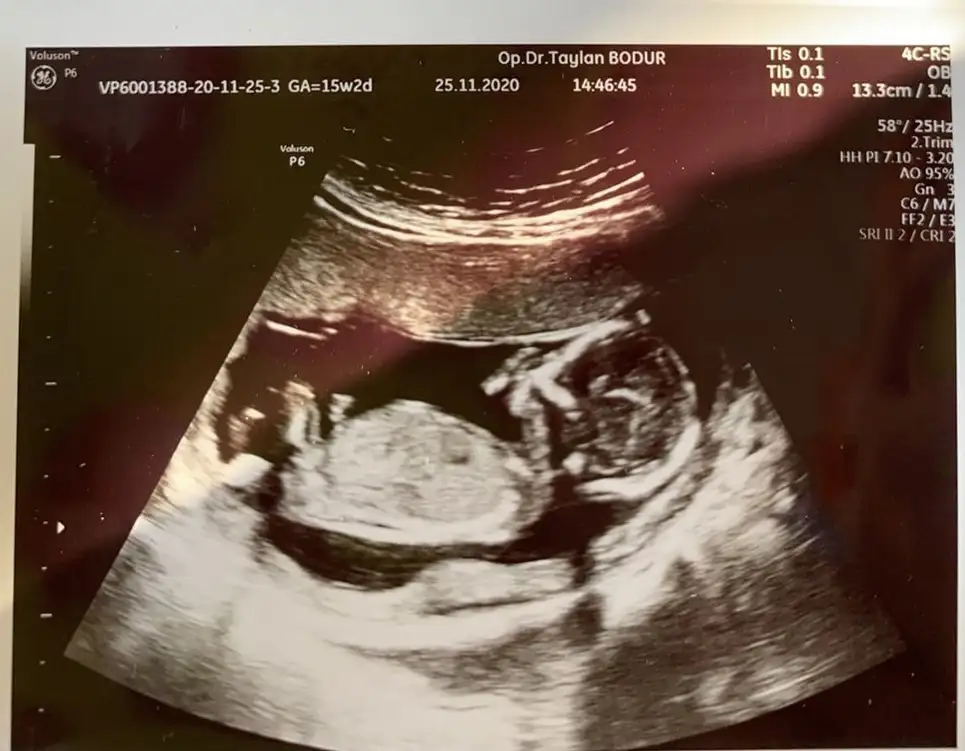

Biraz büyüdük ama buna bakabilir misin 15+2Bunlarda nub gorunmuyor

Kız gibi boş görünüyor bacak arası en iyi 11 12 13 haftalar olmalıBiraz büyüdük ama buna bakabilir misin 15+2